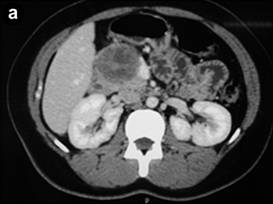

Computed Tomography (CT) of the Abdomen

CT of the abdomen (Figures 2) can identify a circumscribed lesion, usually single, encapsulated, with evidences of internal hemorrhage with tomographic heterogeneous aspects due to the presence of solid and cystic components in different amounts and predominance [1, 15, 16, 17]. Thus, the lesion can consist just of solid components and it can pass through the mixed or solid-cystic form (most common general tomographic presentation) and reach the purely cystic aspect [1, 15, 16, 17]. According to studies by Hu S et al. [16] and Park MJ et al. [15], there is different prevalence between the types of tomographic presentations of pancreatic SPN lesions regarding gender. Thus, the solid-cystic form is the most frequent in women and in men, the form consisting just of solid components prevails [15, 16]. Still, the contrast or understrapper (hyper-density of the image shown in the CT) will be stronger if the amount of existing solid component in the lesion is bigger [1, 15, 16, 17]. Other features able to be evaluated and identified through the CT are: calcification in the capsule, periphery or in the center of the lesion [1, 15, 16, 17]; pancreatic parenchyma around the lesion with normal aspect associated with the non-dilated pancreatic and/or bile ducts [1, 15, 16, 17]; and invasions of vascular structures and neighbor organs, as well as metastases [4, 5, 7]. Finally, the vascularization of the tumor itself is often avascular or little to modestly hyper-vascular, but it is rarely seen [5]. Yet, it is worth talking about the role played by PET-CT when handling pancreatic NSP patients. Unfortunately, there are just a few studies about the use of PET-CT to evaluate these patients. Thus, the few existing studies on this theme are retrospectives with small casuistic [21]. We highlight the uni-institutional retrospective study by Kim Y, et al. [21] which considers the recommendation of PET-CT to evaluate pancreatic NSP patients in order to identify the subtle metastases, especially when it assesses patients with a tumor formed by predominantly solid components.

|

Figure 2. a. Abdominal computerized tomography showing the SPN in the pancreatic head in Case #8. b. Abdominal computerized tomography after body-tail pancreatectomy with splenectomy for SPN (Case #7). |

Sixty percent (60%) of our patients were diagnosed with SPN of with the use CT and MRI scans of the abdomen (Table 2 and Figures 2a and 3). All the patients in our cohort had normal values of the following laboratory studies: complete blood count, coagulation panel (Prothrombin time; International normalized ratio; Partial thromboplastin time; Number of platelets; Bleeding time) amylase, serum creatinine, blood urea, serum albumin, liver profile and also had normal pre-operative tumor markers (like CEA and CA 19.9). The anatomic and pathological examination corroborated the diagnosis of SPN in 90% of the cases. Immunohistochemical studies were necessary to get the final diagnostic confirmation in only one case.